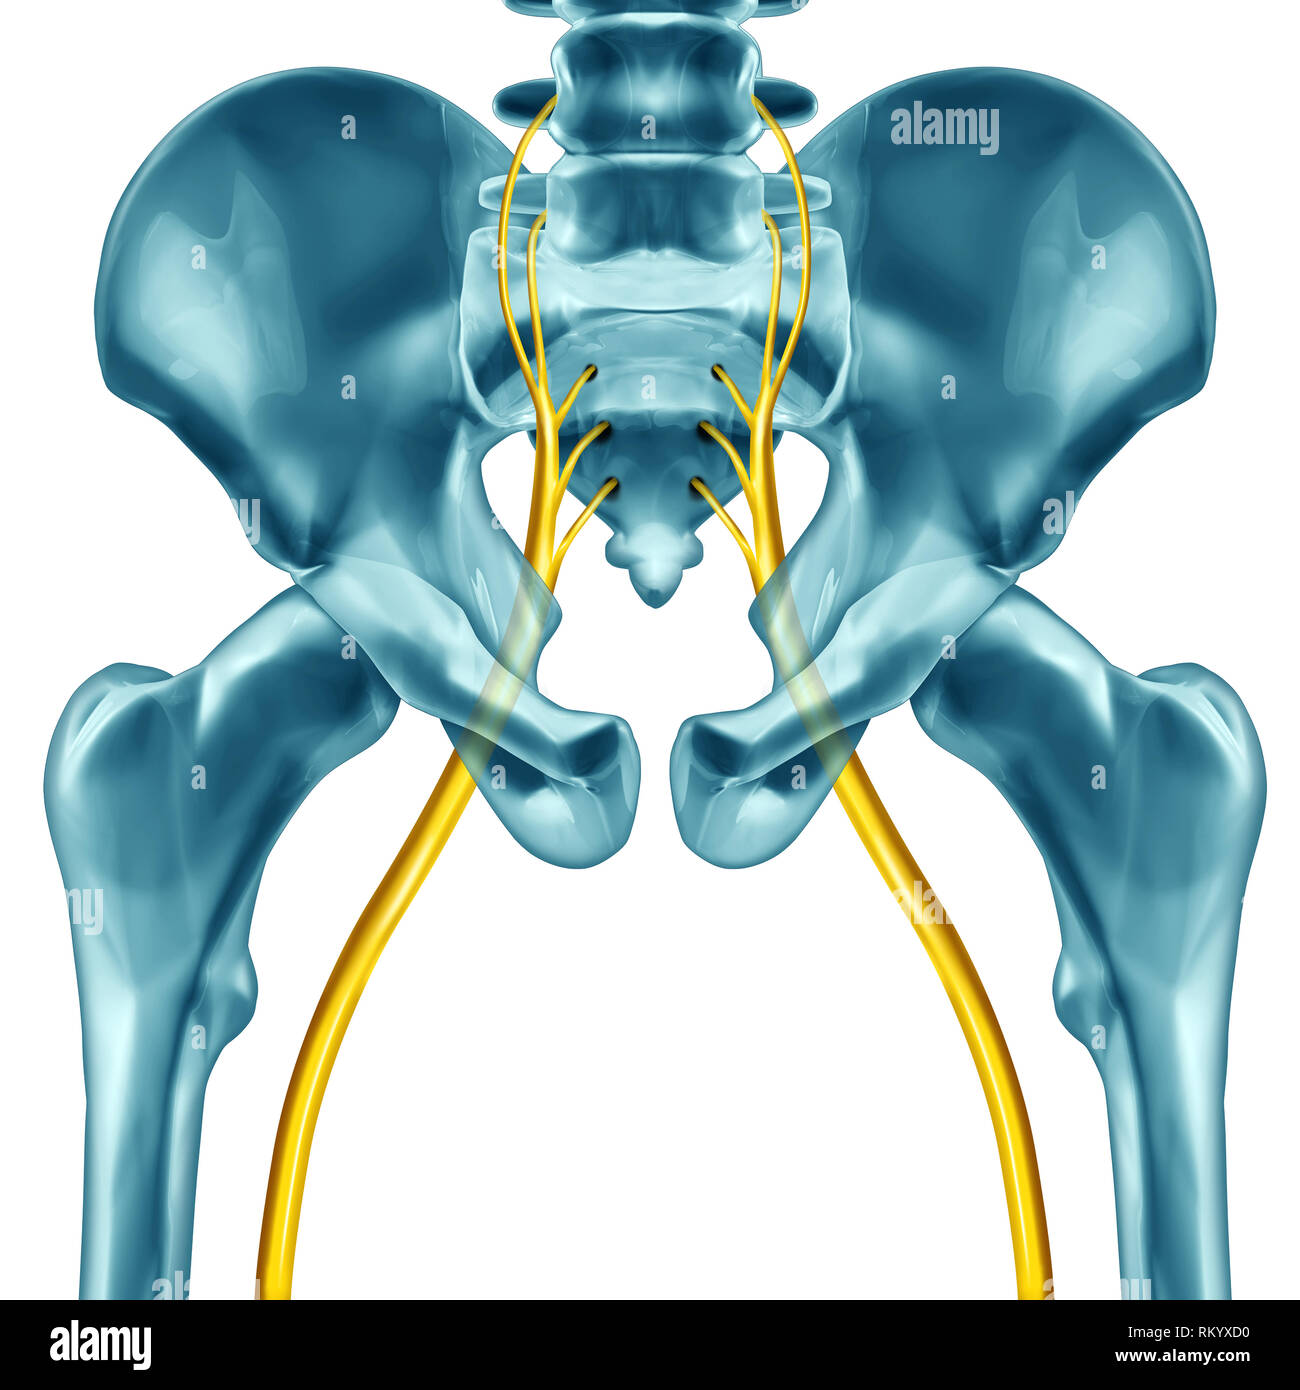

Nerf sciatique concept comme l'anatomie humaine avec 3D illustration d'éléments sur un fond blanc. Banque D'Imageshttps://www.alamyimages.fr/image-license-details/?v=1https://www.alamyimages.fr/nerf-sciatique-concept-comme-l-anatomie-humaine-avec-3d-illustration-d-elements-sur-un-fond-blanc-image236026700.html

Nerf sciatique concept comme l'anatomie humaine avec 3D illustration d'éléments sur un fond blanc. Banque D'Imageshttps://www.alamyimages.fr/image-license-details/?v=1https://www.alamyimages.fr/nerf-sciatique-concept-comme-l-anatomie-humaine-avec-3d-illustration-d-elements-sur-un-fond-blanc-image236026700.htmlRFRKYXD0–Nerf sciatique concept comme l'anatomie humaine avec 3D illustration d'éléments sur un fond blanc.